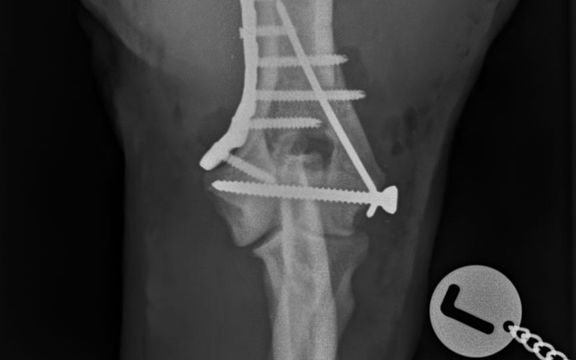

Orthopädische Chirurgie

Operative Versorgung von chronischen Erkrankungen und akuten Verletzungen des Bewegungsapparates, wie z. B. Frakturen (Knochenbrüche) ...

Operationen

Als Operationsmethode der Wahl für Hunde und Katzen aller Größen hat sich bei uns die sogenannte TPLO (Tibial Plateau Leveling Osteotomy) Operation etabliert...